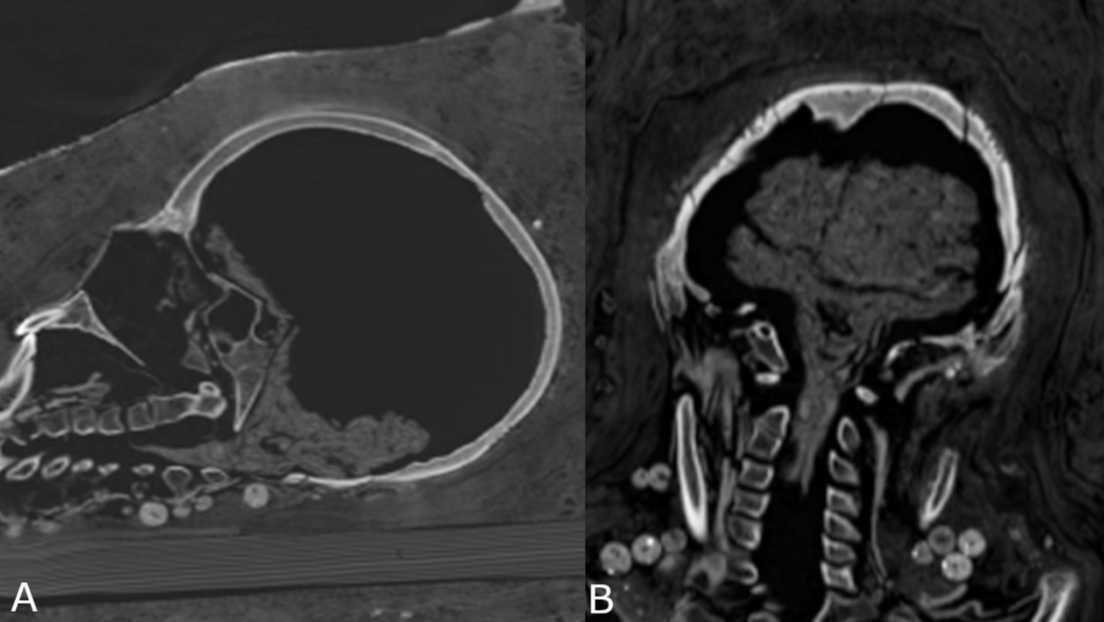

Mediante análisis de tomografía computerizada, lograron obtener información sobre el estado de conservación de los cuerpos, la técnica usada , la edad de los individuos en el momento de la muerte, así como su género, altura y salud.

"Investigaciones radiológicas revelaron que algunas no mostraban evidencia de extirpación del cerebro y de los intestinos”, dijo Stephanie Zesch, investigador principal del estudio.